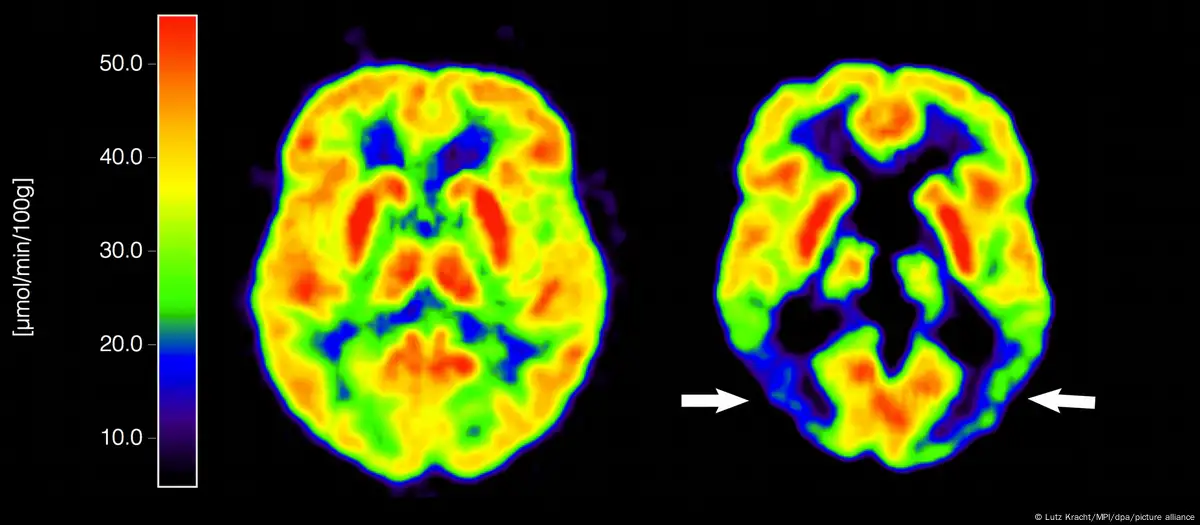

الزائمر کی بیماری بین الاقوامی سطح پر ڈیمنشیا کے مرض کی سب سے عام وجہ ہے اور اس کا تعلق پروٹینز کی ان دو مخصوص لیکن کلیدی اقسام سے ہے، جو دماغ میں پائی جاتی ہیں۔

ان میں سے ایک پروٹین کا نام ایمی لوئڈ (amyloid) ہے جبکہ دوسری ٹاؤ (tau) کہلاتی ہے۔ برطانیہ میں کیے جانے والے بلڈ ٹیسٹ تجربات میں ماہرین کی توجہ ٹاؤ نامی پروٹین کی ایک خاص ذیلی قسم 'پی ٹاؤ 217‘ پر مرکوز رہے گی۔